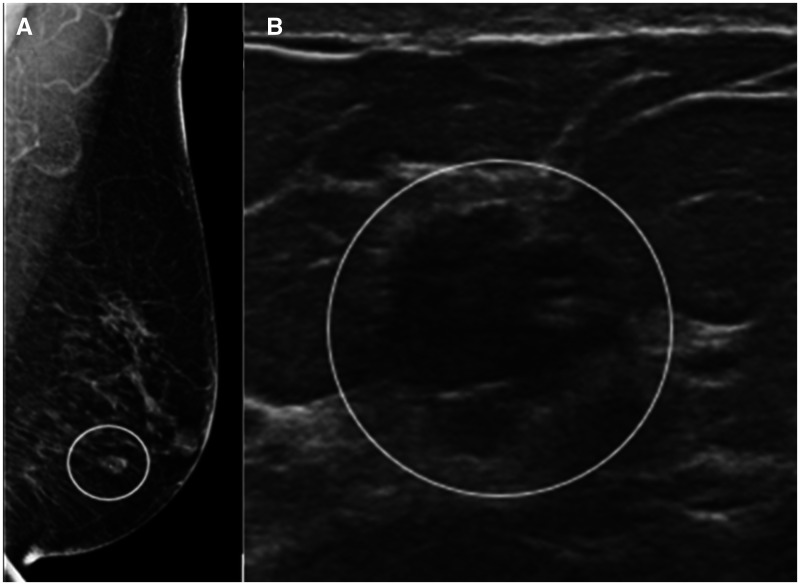

Ductal carcinoma in situ (DCIS) represents a pathologic continuum between a high-risk lesion of the breast and an invasive cancer. Because death from breast cancer is linked to its metastatic spread, the major significance of DCIS is its potential to progress to an invasive cancer and the risk of an occult invasive cancer unrecognized until surgical excision is performed. The standard of care management for DCIS is a minimum of surgical excision, often coupled with adjuvant treatments. For approximately half of the DCIS cases that are at low risk for progression, standard-of-care treatment represents a potential overtreatment and the source of one of the main criticisms against screening. To minimize overtreatment, the tumor biology of any individual's DCIS should be considered in the context of the patient's age, medical comorbidities, and tolerance for risk to tailor personalized treatments. Just as the management of some high-risk lesions of the breast have evolved to include nonsurgical options, it makes sense to personalize the management offered to patients with DCIS. This article reviews the epidemiology, imaging, pathology, ongoing trials, current and possible future treatments of DCIS, comparing and contrasting it with classic high-risk breast lesions and invasive breast cancers.